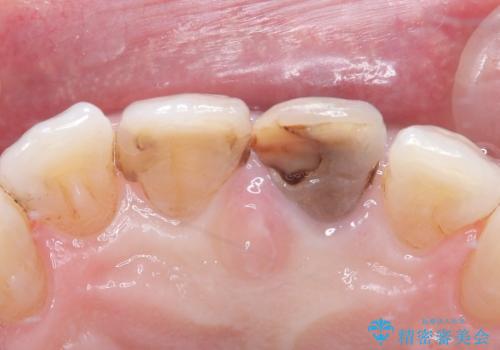

- 歯髄が死んで変色していた歯に対して、根管治療とオールセラミッククラウンでの修復を行いました。まず、根管治療で内部の感染を除去し、歯の強度を高めるためにファイバーコアを装着しました。その後、審美性と耐久性を考慮し、オールセラミッククラウンで覆うことで、自然な歯の色合いに近い美しい仕上がりを実現しました。

歯髄が死んだ歯は通常の健康な歯に比べて透過性が低く、特有の暗い色調を帯びる傾向にあります。変色は時間とともに進行し、薄い茶色や灰色、黄色がかった色合いになることが多いです。このような変色は、審美的な面で気になる場合が多く、オールセラミッククラウンなどでの修復が行われることも一般的です。